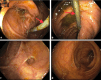

Endoscopic biliary stenting is a well-established intervention for the treatment of biliary, hepatic, and pancreatic disorders. The common indications include strictures, neoplasms, stones, infections, and bile leaks. Stents can be occluded, predisposing patients to ascending cholangitis and biliary sepsis. Distal stent migration is another known complication of endoscopic stenting and is usually spontaneous. Bowel perforation, abscesses, bleeding, and pancreatitis are rare complications of distal stent migration and are usually limited to the duodenum. Herein, we describe an extremely rare case of bilio-cecal stent migration presenting as rectal bleeding.